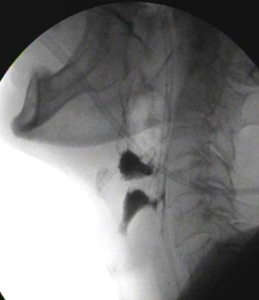

X線透視装置を使用した検査のひとつに「嚥下造影」があります。

嚥下造影とは、飲み込みの過程や状態を評価するための検査で

摂食・嚥下障害の疑われる患者さんに対して行います。

嚥下造影(正常) 嚥下造影(誤嚥)